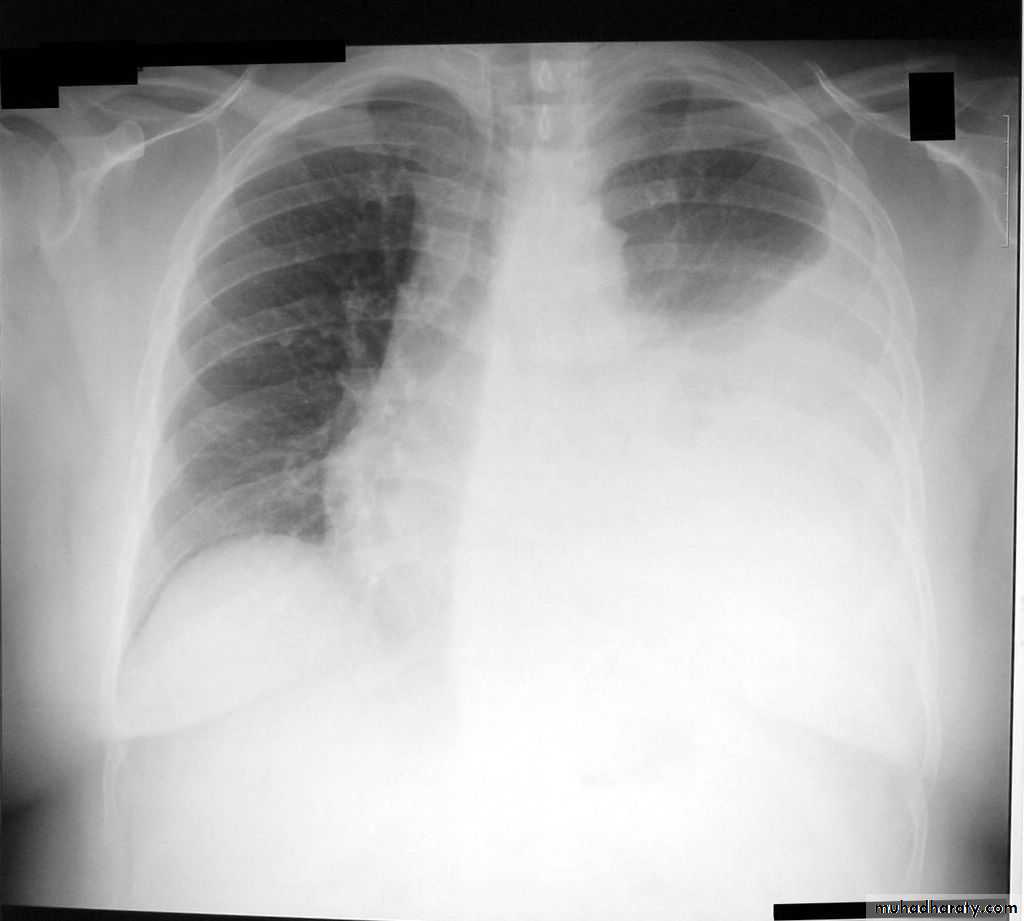

CXR:

Tension Pnenmothorax